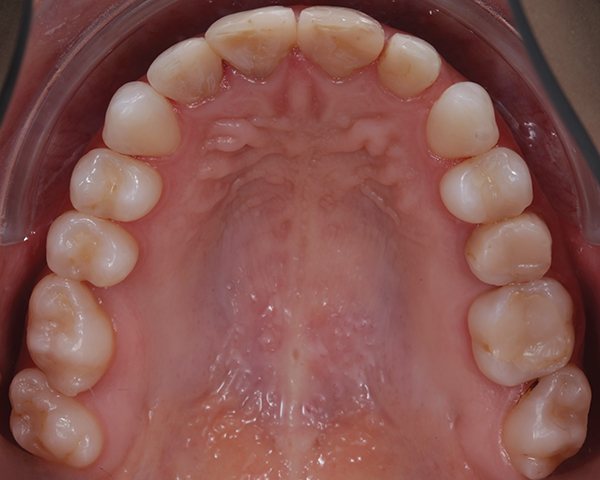

The interdisciplinary treatment plan to establish good oral health, esthetics, and function included prophylaxis and oral hygiene instructions as first steps. Respective teeth were extracted and orthodontic treatment was carried out. Figure 4 and Figure 5 depict the intraoral situation before orthodontic treatment with fixed appliances and ceramic brackets; Figure 6 through Figure 8 show the situation after orthodontic treatment, which lasted 18 months.

Fig 4. Preoperative intraoral occlusal views of the maxillary (Fig 4) and mandibular (Fig 5) arches.

Figure 4